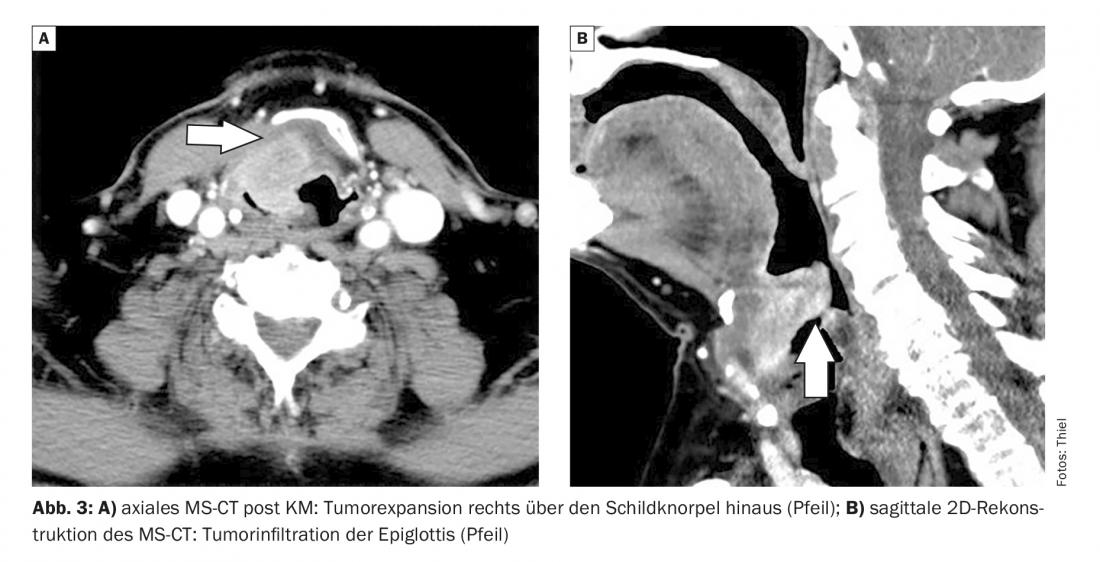

O relatório de caso 3 documenta uma massa tumoral inicialmente necrótica central num 71 fumador (50-60 PY) com rouquidão crescente, estendendo-se desde a laringe supraglótica até à epiglote. A cartilagem da tiróide é arrojada, o limite do órgão é excedido. Para além das metástases dos gânglios linfáticos cervicais, as filas pulmonares também estavam presentes na TC do tórax (Fig. 3A e B).